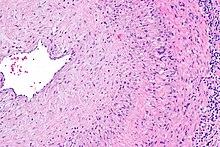

Intermediate magnification micrograph showing giant cell arteritis in a temporal artery biopsy. The arterial lumen is seen on the left. A giant cell is seen on the right at the interface between the thickened intima and mediaH&E stain

The gold standard for diagnosing temporal arteritis is biopsy, which involves removing a small part of the vessel under local anesthesia and examining it microscopically for giant cells infiltrating the tissue.[21] However, a negative result does not definitively rule out the diagnosis; since the blood vessels are involved in a patchy pattern, there may be unaffected areas on the vessel and the biopsy might have been taken from these parts. Unilateral biopsy of a 1.5–3 cm length is 85-90% sensitive (1 cm is the minimum).[22] A Characterised as intimal hyperplasia and medial granulomatous inflammation with elastic lamina fragmentation with a CD 4+ predominant T cell infiltrate, currently biopsy is only considered confirmatory for the clinical diagnosis, or one of the diagnostic criteria.[11]